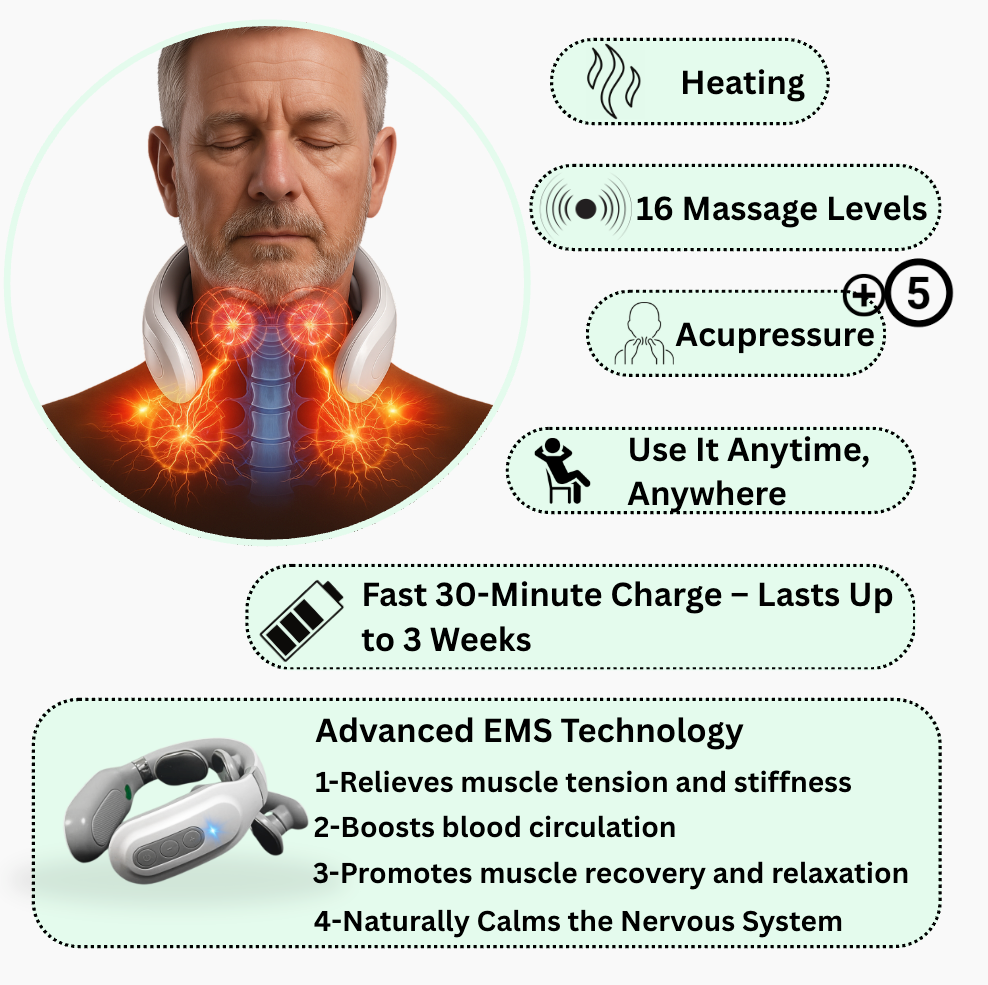

To increase the EMS (electro-muscle stimulation) intensity, simply press the plus (+) button in short clicks until you reach the level you want (up to level 16).